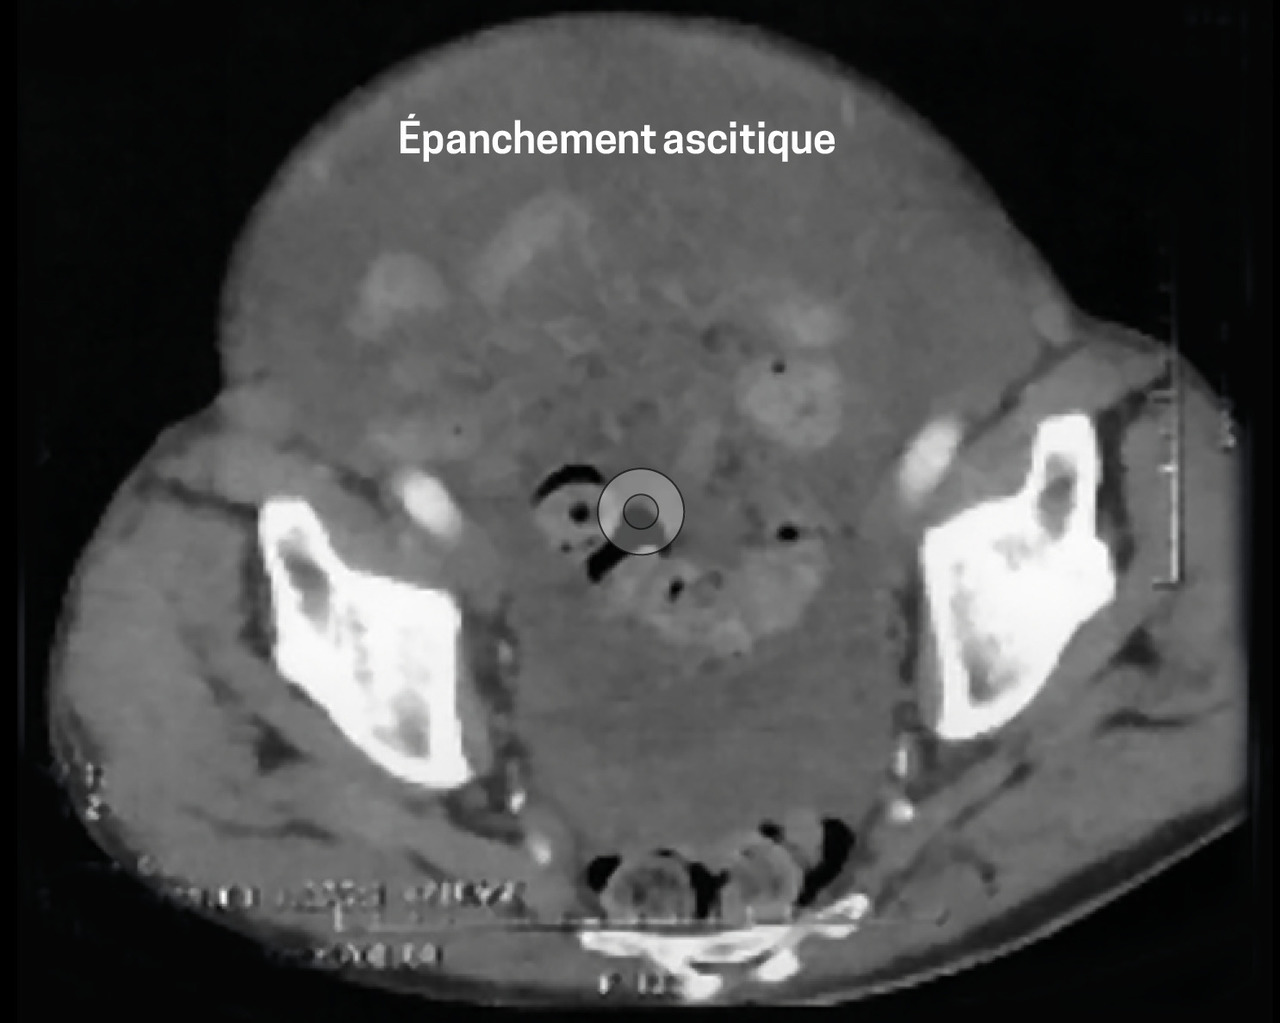

Le scanner abdominal (fig. 1 et 2)montre un volumineux épanchement ascitique diffus, un foie dysmorphique. Le bilan d’hépatopathie est négatif. L’ACE est élevé (8,79 µg/L), comme le CA 19,9 (57 UI/mL).

L’échographie révèle une ascite multi-cloisonnée. La ponction retrouve un liquide gélatineux ; l’analyse anatomopathologique est en faveur d’une maladie gélatineuse du péritoine.

La tomodensitométrie et l’échographie apportent des signes radiologiques complémentaires : respectivement encoches hépatiques et images de cloisons.